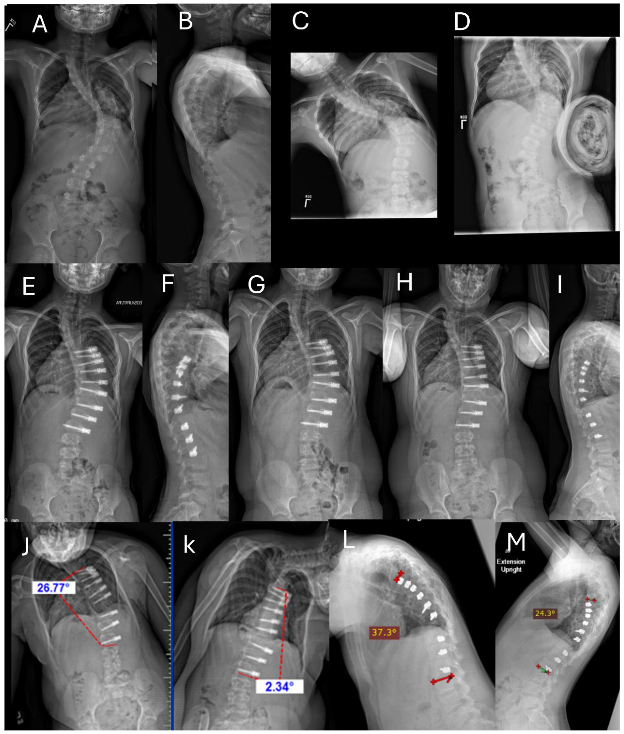

Fig. 2A-L. Example of unilateral thoracic ASC with intervertebral de-tethering releases.